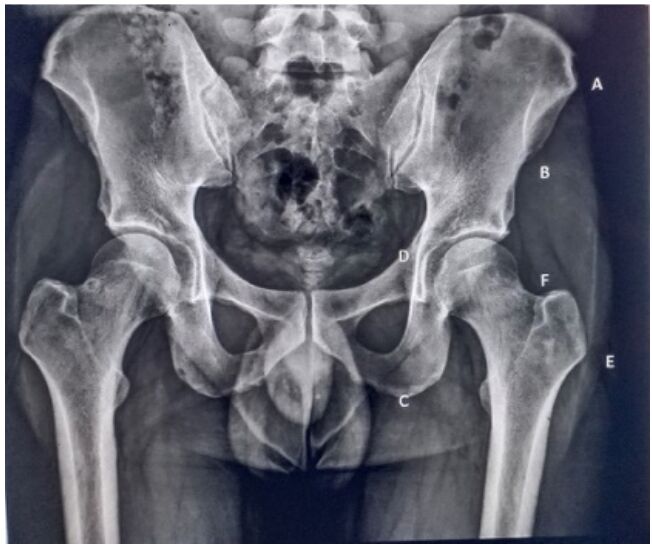

24.關於骨盆X光(如附圖所示)之敘述,下列何者正確?

(A)A為骨盆最寬處 (B)B為AIIS (C)E為股骨頸 (D)C為縫匠肌附著